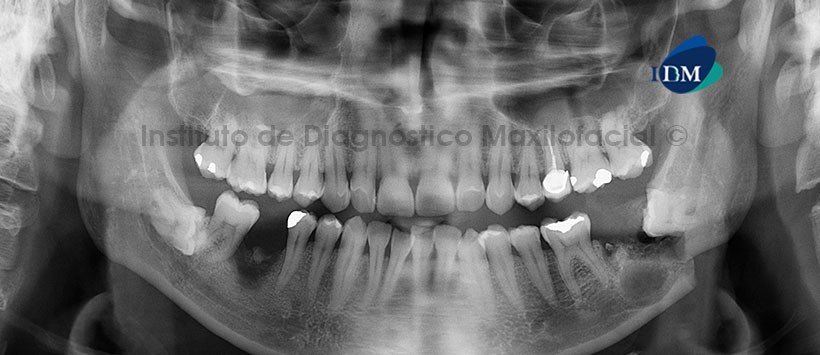

A la evaluación de la radiografía panorámica se aprecia trazo de fractura que se extiende del reborde alveolar correspondiente a la pieza 3.7 hacia el reborde basal mandibular, asociada a la corona de la pieza 3.8. Así mismo se aprecia una imagen radiolúcida de limites definidos y bordes parcialmente corticalizados asociada a la fractura. Se aprecia lecho alveolar correspondiente a la pieza 3.7. (Figura 1)